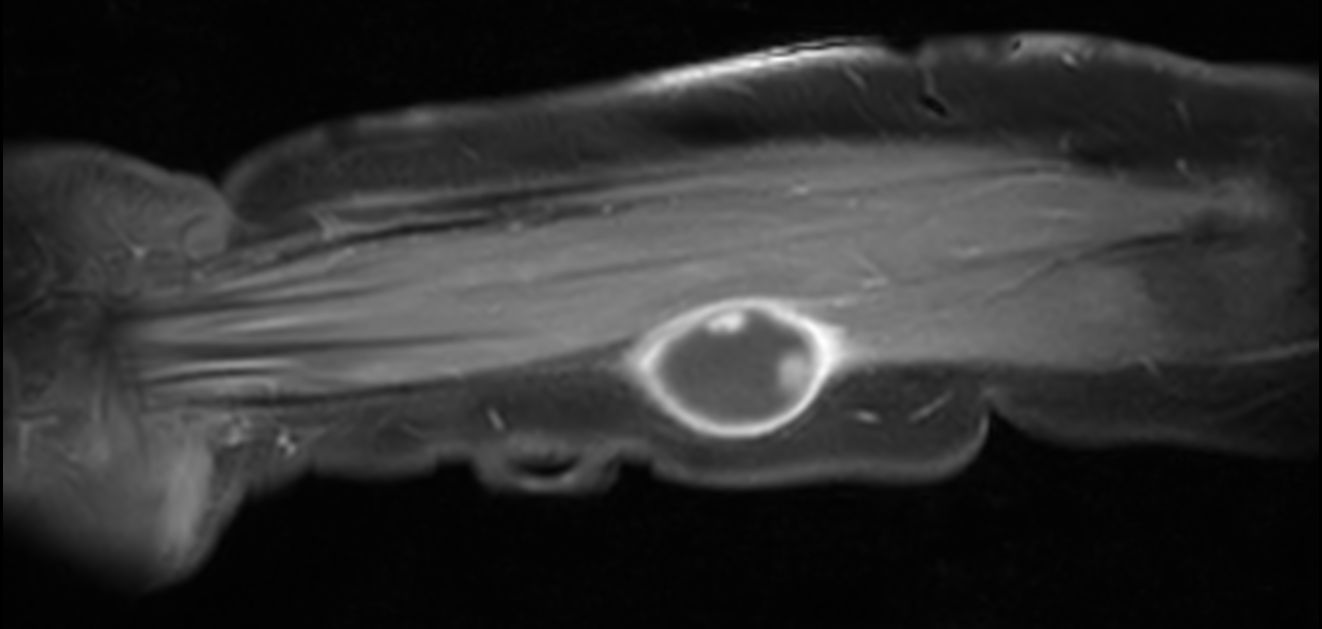

Pediatric patient with a lesion in the forearm. mDIXON XD provides uniform fat-free imaging and allows for multiple image types in one single scan. Integration of Compressed SENSE acceleration technique enables speeding up of the entire exam.

Axial T1w TSECompressed SENSE